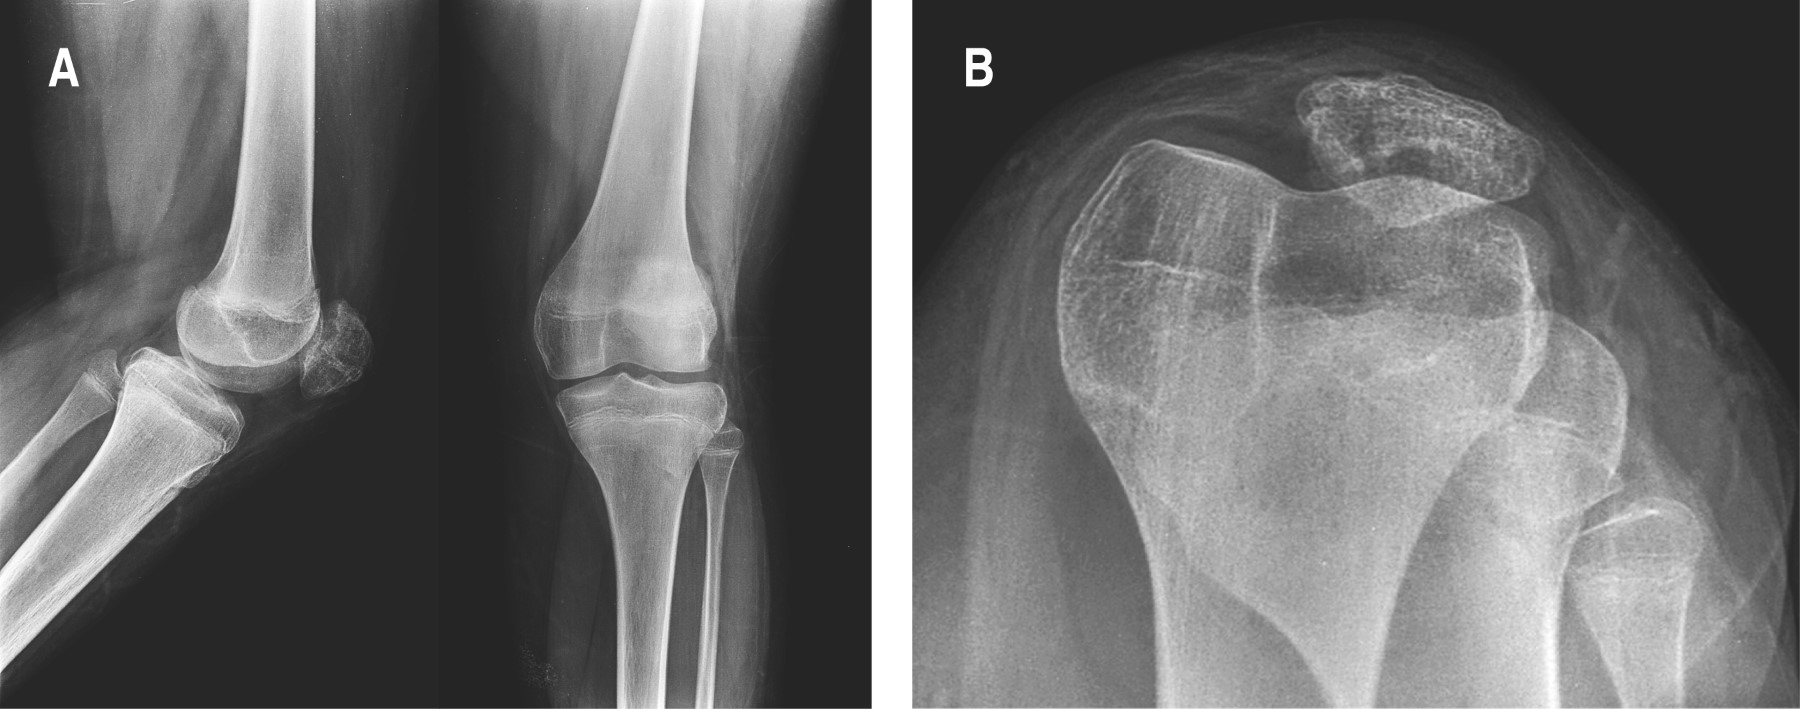

Se realizó retiro de material de osteosíntesis a los 14 meses de evolución, sin complicaciones. Se tomaron radiografías de control anteroposterior, lateral y axiales que mostraron adecuada consolidación, sin datos de desplazamiento o soluciones de continuidad, con adecuada congruencia articular, así como un correcto espacio femoropatelar (Figura 5).

Figura 5

Figura 6